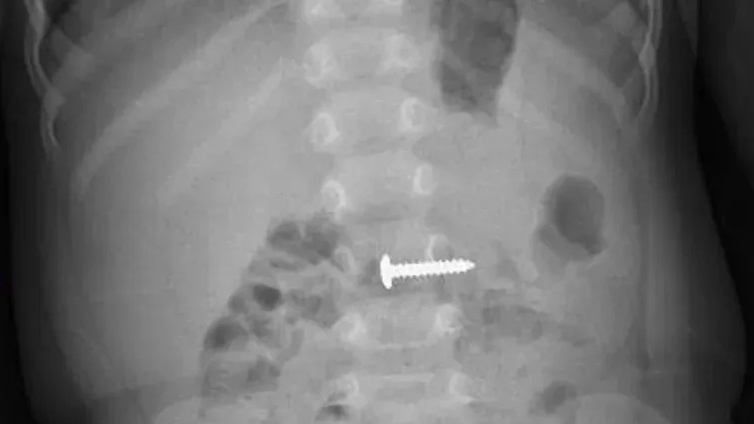

GS.TS Trần Bình Giang (người đứng giữa) trong một ca can thiệp nội soi tiêu hóa cho người bệnh.